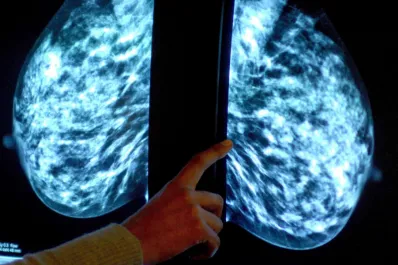

Tucumán contra el cáncer de mama: charlas y eventos deportivos para concientizar en el Octubre Rosa

El Ministerio de Salud Pública compartió las actividades que se realizarán hasta fin de mes.

Cinco datos que tenés que saber sobre el cáncer de mama

Durante todo octubre autoridades sanitarias llevarán adelante una campaña de concientización sobre la importancia de la prevención y detección temprana.